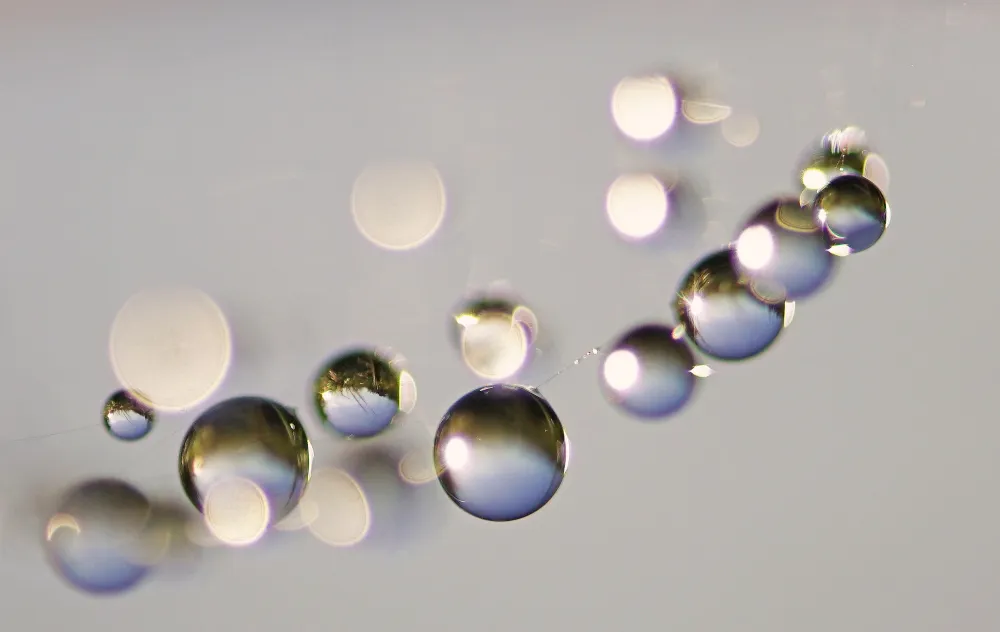

Ovaries together with immature eggs develop early during fetal development before birth. Therefore, a newborn girl has already a stock of immature eggs in her ovaries. These eggs remain immature until she reaches puberty when the body’s hormonal system becomes active and stimulates maturation of eggs. Consequently, puberty is an important factor when fertility preservation is planned. If the patient has undergone puberty, the possibility to collect mature eggs to preserve fertility should be considered. If the patient has not gone through puberty, there are no mature eggs available, and the only option to preserve fertility is to collect and cryopreserve a piece of ovarian tissue that contains immature eggs.

Sometimes ovarian tissue is collected for fertility preservation in adult women too. For example, if cancer treatments must be started immediately, ovarian tissue collection is the only procedure that can be performed rapidly because collection of mature eggs takes several weeks. A piece of ovarian tissue is surgically removed and stored in -180 °C. When the woman has recovered from cancer and wishes for pregnancy, the frozen ovarian tissue can be thawed and transplanted back. There are over 130 babies born after ovarian tissue transplantation in the world. The method is now considered established clinical routine for adult women. However, information on the suitability of this procedure for young girls is limited. There are only two known cases where ovarian tissue collected from girls have led to pregnancies after transplantation. In these cases, the girls were around 10 years old when the ovarian tissue was removed. We do not know if the method works for even younger patients. Importantly, tissue transplantation is not an option for all patients because the tissue may contain cancer cells that could return to the patient. This is the case for blood cancers like leukemias and lymphomas. For these patients, maturation of eggs in the laboratory could be an option in the future. However, no such method exists today.

- What kind of cells is child ovarian tissue made of? Are these cells similar to those in adult ovarian tissue?

- How similar are the immature eggs in child ovaries compared to those in adult ovaries?

- Can immature eggs from child ovaries be matured in the laboratory?